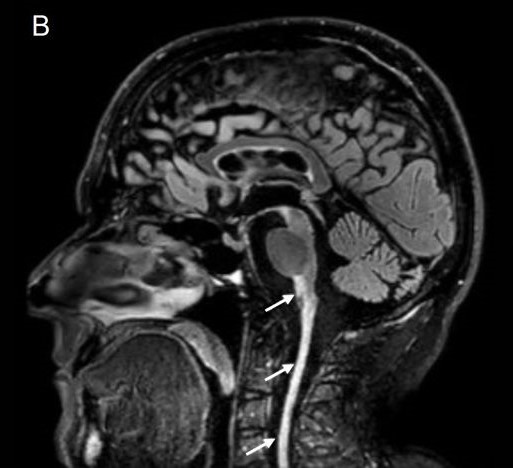

šļøš Syrinx in spontaneous intracranial hypotension treated by surgical disconnection of CSF venous fistula ā¬ļø (š) āļø @_davidrowland et al. via @PracticalNeurol

A 49-year-old woman developed symptoms of syringomyelia 3 years after having presented with spontaneous intracranial hypotension (SIH). She had previously undergone two unsuccessful non-targeted...